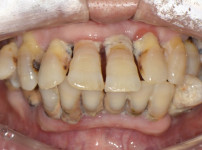

상악전치부 심미보철

최OO님/치료기간:2주/상악전치...